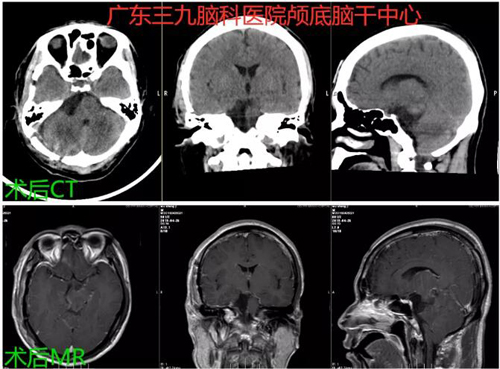

图3:术后CT及MR示右侧桥小脑角区占位病变切除术后改变